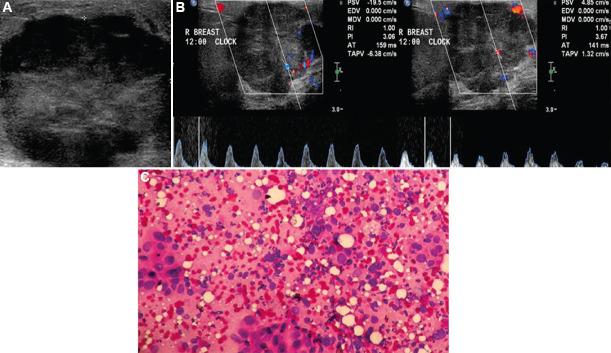

BACKGROUND & OBJECTIVES: : Ultrasound BI-RADS categories 3 and 4 constitute those breast masses which cannot be confidently classified as benign or malignant, owing to their morphological characteristics. These masses are further managed by follow up and biopsy, respectively. This study aims to evaluate the role of strain elastography and Doppler in better characterization of these sonographically indeterminate breast masses as benign or malignant.

: Fifty female patients with ultrasound BI-RADS 3 or 4 were evaluated with strain elastography and color Doppler including spectral analysis. Eight variables were assessed by elastography and Doppler, including a new phenomenon called bidirectional arterial flow (BAF). The findings were correlated with the gold standard diagnostic method of histopathology/cytology. Based on findings of combined elastography and Doppler method, the initial ultrasound BI-RADS categories of masses were re-categorized by up-gradation or down-gradation. Sensitivity, specificity, accuracy, positive predictive value, negative predictive value and receiver operating characteristic (ROC) curves were used to estimate the diagnostic performance of the combination method.

: Using ROC analysis, the positivity of ≥3 among the total eight variables correlated with malignancy on histopathology. Sensitivity, specificity and accuracy of the combination method using cut-off score ≥3 (i.e. at least three out of the eight parameters in the combination method being positive) for the prediction of malignancy was 100, 76.47 and 92 per cent, respectively, with the area under curve being 0.967. In addition, BAF was found predictive of malignancy with a diagnostic accuracy of 70 per cent.